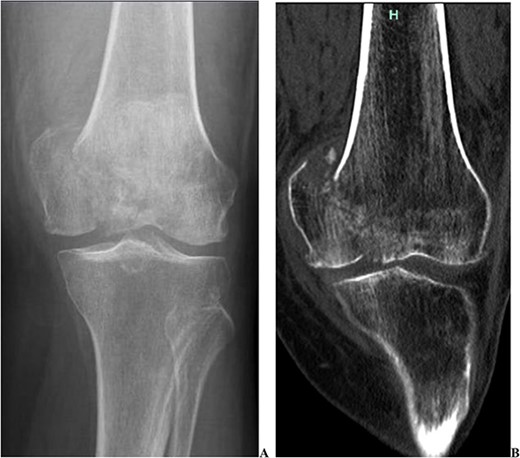

We present the case of a 76 year old Hispanic female previously managed for tri-compartmental osteoarthritis and lateral condyle insufficiency fracture of the left knee. She was being managed conservatively; however, the pain began to affect her well-being and activities of daily living (ADL). Most recently the patient suffered a mechanical ground level fall resulting in an ipsi-lateral medial condyle fracture as seen in Fig. 1. Single staged left knee medial condyle ORIF and CCK arthroplasty through a medial para-patellar approach was performed. The medial condyle fracture was reduced and stabilized using a 5-hole distal fibula locking plate in buttress mode. After fracture stabilization, a CCK arthroplasty was performed. Immediate post-operative imaging is seen in Fig. 2. Intra-operative photos are demonstrated in Fig. 3. The patient was made non-weight bearing for 2 weeks followed by weight bearing as tolerated (WBAT). An early weight bearing protocol was used given the majority of forces during ambulation would be placed through the total knee implant and not place significant stress on the medial condyle ORIF. At 3 months post-operatively, the patient obtained 0–120° range of motion (ROM) and was freely WBAT. At 8 weeks, however, the patient required a manipulation under anesthesia for regressing to 0–95° ROM. Figure 4 demonstrates intra-operative images of the manipulation. At 3 years follow up, her ROM was 5–95 with good strength without any further complication or subsequent procedures. Three years post-operatively the patient reported improved function with ADLs, significantly improved pain, and better mental health.

Two intra-operative images demonstrating the pre-manipulation flexion of 70°, and the post-manipulation flexion of 115°.